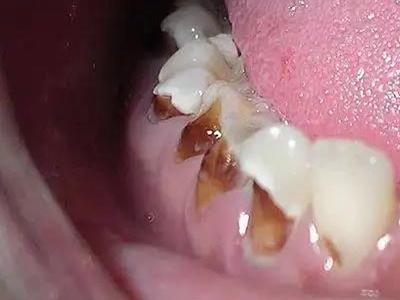

酸蚀症牙齿缺损严重有黑斑图

酸蚀症严重时会使牙齿出现大面积缺损,有三颗下牙损毁严重,露出不整齐的牙骨质边缘,几乎仅余留牙根。缺损处有黑斑,局部呈黄褐色,需积极就医进行牙齿修复。

酸蚀症牙齿有大量黑斑并缺损图

酸蚀症严重时,牙齿会有大量黑斑,呈黄褐色至黑褐色,且牙齿大范围缺损,仅遗留不规则团块状牙骨质,需积极就医进行牙齿修复治疗。

酸蚀症后排牙齿大量缺损图

酸蚀症患者的后排牙齿可发生大量缺损,一侧牙齿遗留圆盘状牙根,形似被切割,另一侧牙齿有大量凹陷坑洞,部分牙齿颜色发黑或呈黄褐色,其发生与长期接触酸性物质有关。